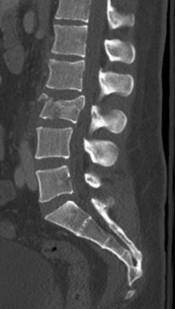

Question 22:

A 54-year-old male with a history of intravenous drug use presents with severe back pain, fever, and progressively worsening bilateral lower extremity weakness over the last 48 hours. A representative MRI is shown below. Given the classic findings for this pathology, what is the most likely causative organism, and what is the standard definitive treatment?

Correct Answer: Staphylococcus aureus; urgent surgical decompression and targeted antibiotics

Explanation:

The clinical scenario and presumed MRI findings (epidural fluid collection causing cord compression) are classic for a spinal epidural abscess. The most common causative organism overall, and specifically in intravenous drug users, is Staphylococcus aureus. Because the patient is exhibiting progressive neurologic deficits (lower extremity weakness), urgent surgical decompression (usually a laminectomy) combined with targeted intravenous antibiotics is the standard definitive treatment to prevent permanent neurologic injury.